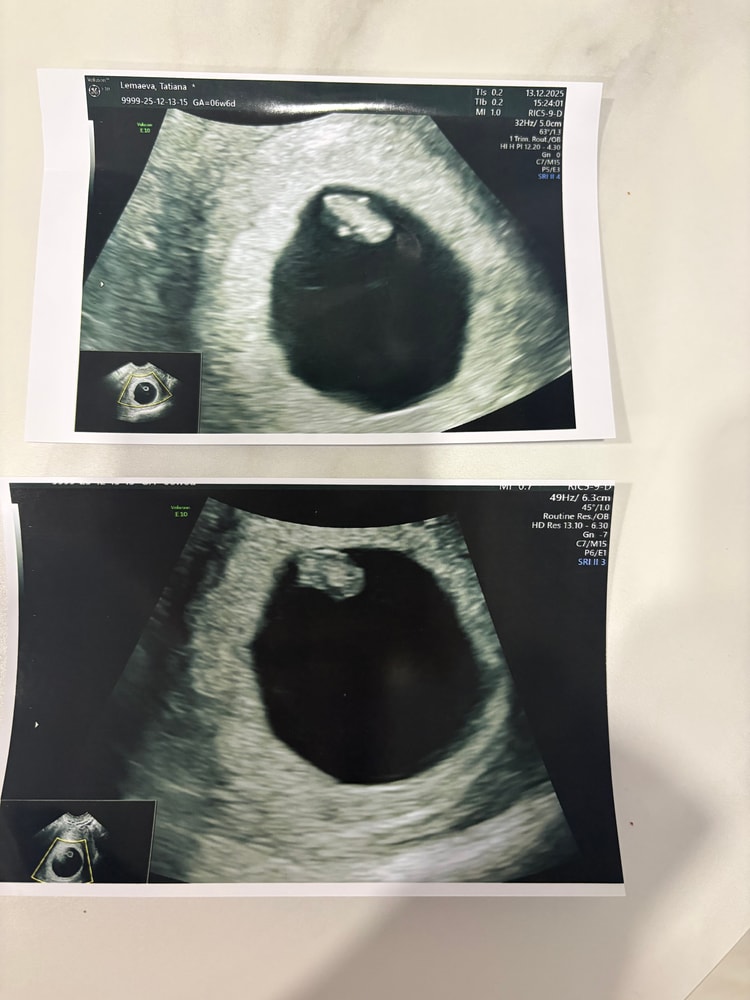

Мария, вагинально? Какой срок?

16 часов

Юлия *, вагинально, срок 6,5

Мария, по Рамзи девочка